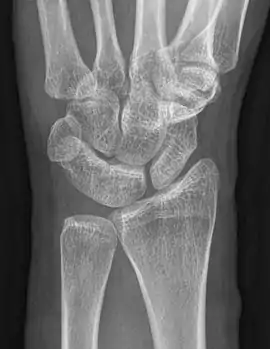

| An example of a lunotriquetral coalition, the most commonly fused carpal bones | |

Carpal coalition is the abnormal fusion of two or more carpal bones when they fail to segment during intrauterine development.[1] First described by Eduard Sandifort in 1779, carpal coalitions are often an isolated issue which connect two carpal bones in the same row of the wrist.[2] These issues are congenital and occur at various rates throughout the population.[3]

The lunate and triquetral bones are the most common carpal bones to fuse together, resulting in a lunotriquetral coalition in 1% of people. 60% of patients with a lunotriquetral coalition will have it bilaterally.[1] Among isolated incidents the capitate and hamate bones are the next most common to fuse followed by the pisiform-triquetrum, trapezium-trapezoid, scaphoid-capitate, and triquetrum-hamate.[3]